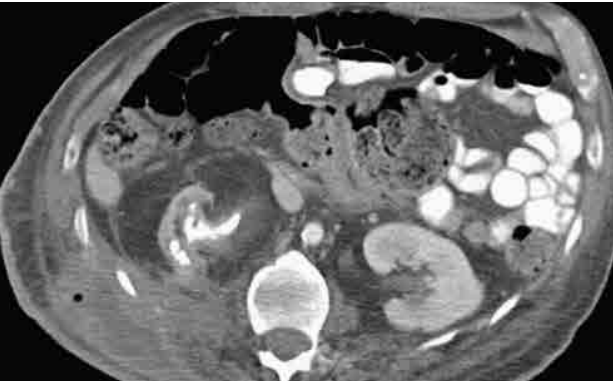

Mulher de setenta anos de idade, obesa, portadora de diabetes mellitus e histórico de nefrolitíase dá entrada no pronto-socorro com dor lombar à direita há três dias, febre aferida, diminuição da diurese e mantendo estabilidade hemodinâmica. Foram realizados exames laboratoriais, que evidenciariam o aumento de provas inflamatórias, escórias nitrogenadas e urina tipo 1 infecciosa. Também foi realizada tomografia de abdome e pelve, com contraste endovenoso.

Com base nesse caso hipotético e considerando a avaliação do corte tomográfico na imagem acima e a hipótese diagnóstica, a conduta correta na urgência será